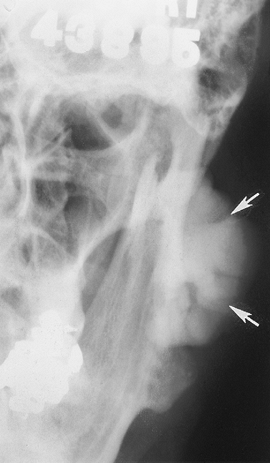

![]() |

FIGURE 2-9 Coronal MRI in a patient with RA. There is extensive pannus formation bilaterally (arrows).

Multiple arthropathies can affect the

TMJ: rheumatoid arthritis (RA), juvenile chronic arthritis, psoriatic

arthritis, ankylosing spondylitis, systemic lupus erythematosus, gout,

and other crystal arthropathies. -

Some 28% to 63% of patients with juvenile chronic arthritis have TMJ involvement.

-

RA involving the TMJ is three times more common in females.

Up to 50% of patients with severe RA have TMJ involvement.

Patients may have joint erosions, laxity, and malocclusion.

MRI with contrast enhancement is most useful for complete evaluation of TMJ arthropathies.